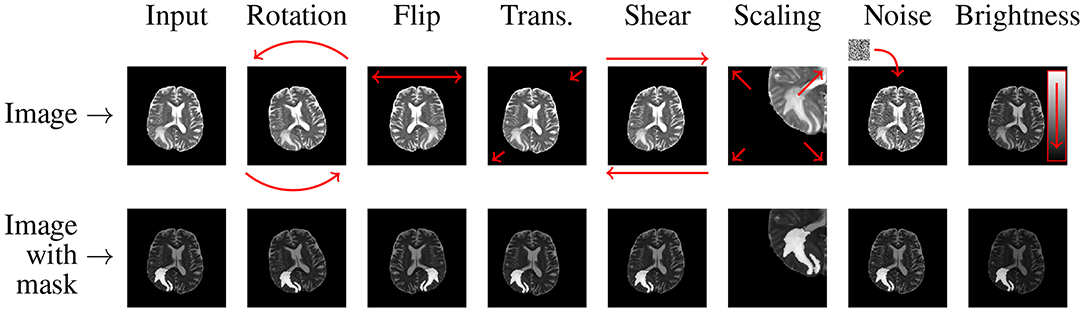

Geometric transformations alter the spatial layout of an image while preserving its semantic meaning. Typical operations include:

- Flipping: Random horizontal (and sometimes vertical) flips mirror the image without changing the label. For example, a horizontal flip creates a left-right mirrored copy. But when using vertical flipping, we need more care, since some domains, such as medical imaging, may treat upside-down content as unrealistic (domain-dependent).

- Rotation: Rotating images by small random angles theta ( ±45°) simulates different viewpoints and helps models handle cases where objects are not perfectly aligned.

- Shearing: Shearing applies a non-affine transformation that shifts one part of an image along an axis to introduce perspective changes while holding the other fixed. It is handy in OCR to handle italicized or slanted handwriting.

- Brightness and Contrast Adjustment: It involves brightness adjustment (randomly brightening or darkening an image) or altering contrast to mimic different lighting conditions. For instance, increasing brightness helps the model cope with sunny conditions, and darkening simulates shadows.

- Gaussian Noise Injection: Adding random Gaussian noise simulates sensor noise or low-light grain.

Image data augmentation using rotation, scaling, flipping, and elastic deformations can generate varied yet realistic training images from a small existing dataset.